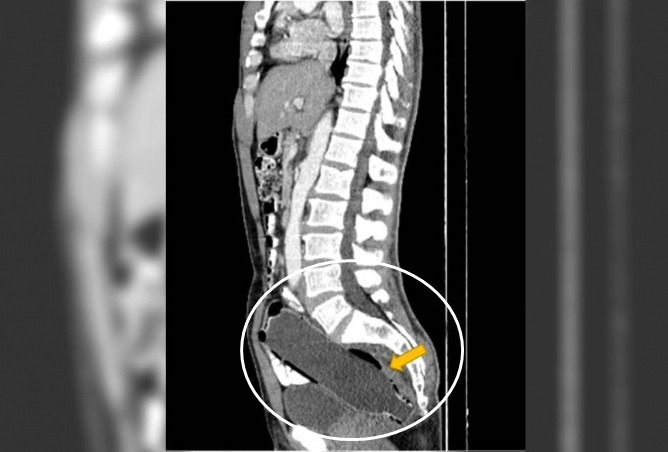

Kết quả chụp X-quang cho thấy điều lạ. Nhìn kỹ, bác sĩ vô cùng ngạc nhiên, choáng váng khi phát hiện trong trực tràng của người đàn ông có một khối vật thể lạ dài khoảng 19,05 cm.

Sau đó, dưới sự khuyên giải của bác sĩ và tình trạng đau đớn diễn tiến nặng, người đàn ông cũng chịu thừa nhận, anh đã nhét vật thể lạ, cũng chính là chiếc chai nhựa nguyên sinh vào hạ thể của mình.

Bác sĩ không đề cập đến việc chiếc lọ được đưa vào như thế nào, nhưng tiết lộ rằng phần đáy của chiếc lọ đã đi vào trước và không may bị kẹt lại bên trong.

Sau đó, người đàn ông được đưa vào phòng mổ, bác sĩ từ từ lôi chai nhựa ra ngoài để giảm thiểu tổn thương cho ruột. Một tháng sau ca phẫu thuật, tình trạng của người đàn ông hồi phục tốt mà không có vấn đề gì. Hiện, sau khi vết thương ổn định, bác sĩ đã chuyển người đàn ông đến Khoa Tâm thần để điều trị thêm.